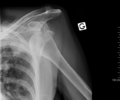

Dislocated shoulder X-ray 10.png

خلع أمامي للكتف الأيسر.

الكتف المخلوع أو خلع الكتف، هي حالة طبية تحدث عند انفصال عظمة العضد عن مفصل الكتف.[2] وتشمل أعراض خلع الكتف آلام في الكتف وعدم استقراره.[2] وتشمل المضاعفات المحتملة لخلع الكتف آفة بانكارت، آفة هل-ساكس، تمزق الكفة المدورة، أو إصابة العصب الإبطي.[1]

عادة ما يحدث خلع الكتف نتيجة لسقوط الشخص على ذراعه وهي ممدودة أو سقوطه على الكتف.[4] عادة ما يعتمد التشخيص على العلامات الظاهرة على الحالة ويتم التأكد عن طريق التصوير بأشعة إكس.[2] تصنف حالات خلع الكتف إلى خلع أمامي، خلفي، سفلي، وعلوي والأكثر شيوعاً هو خلع الكتف الأمامي.[2][1]